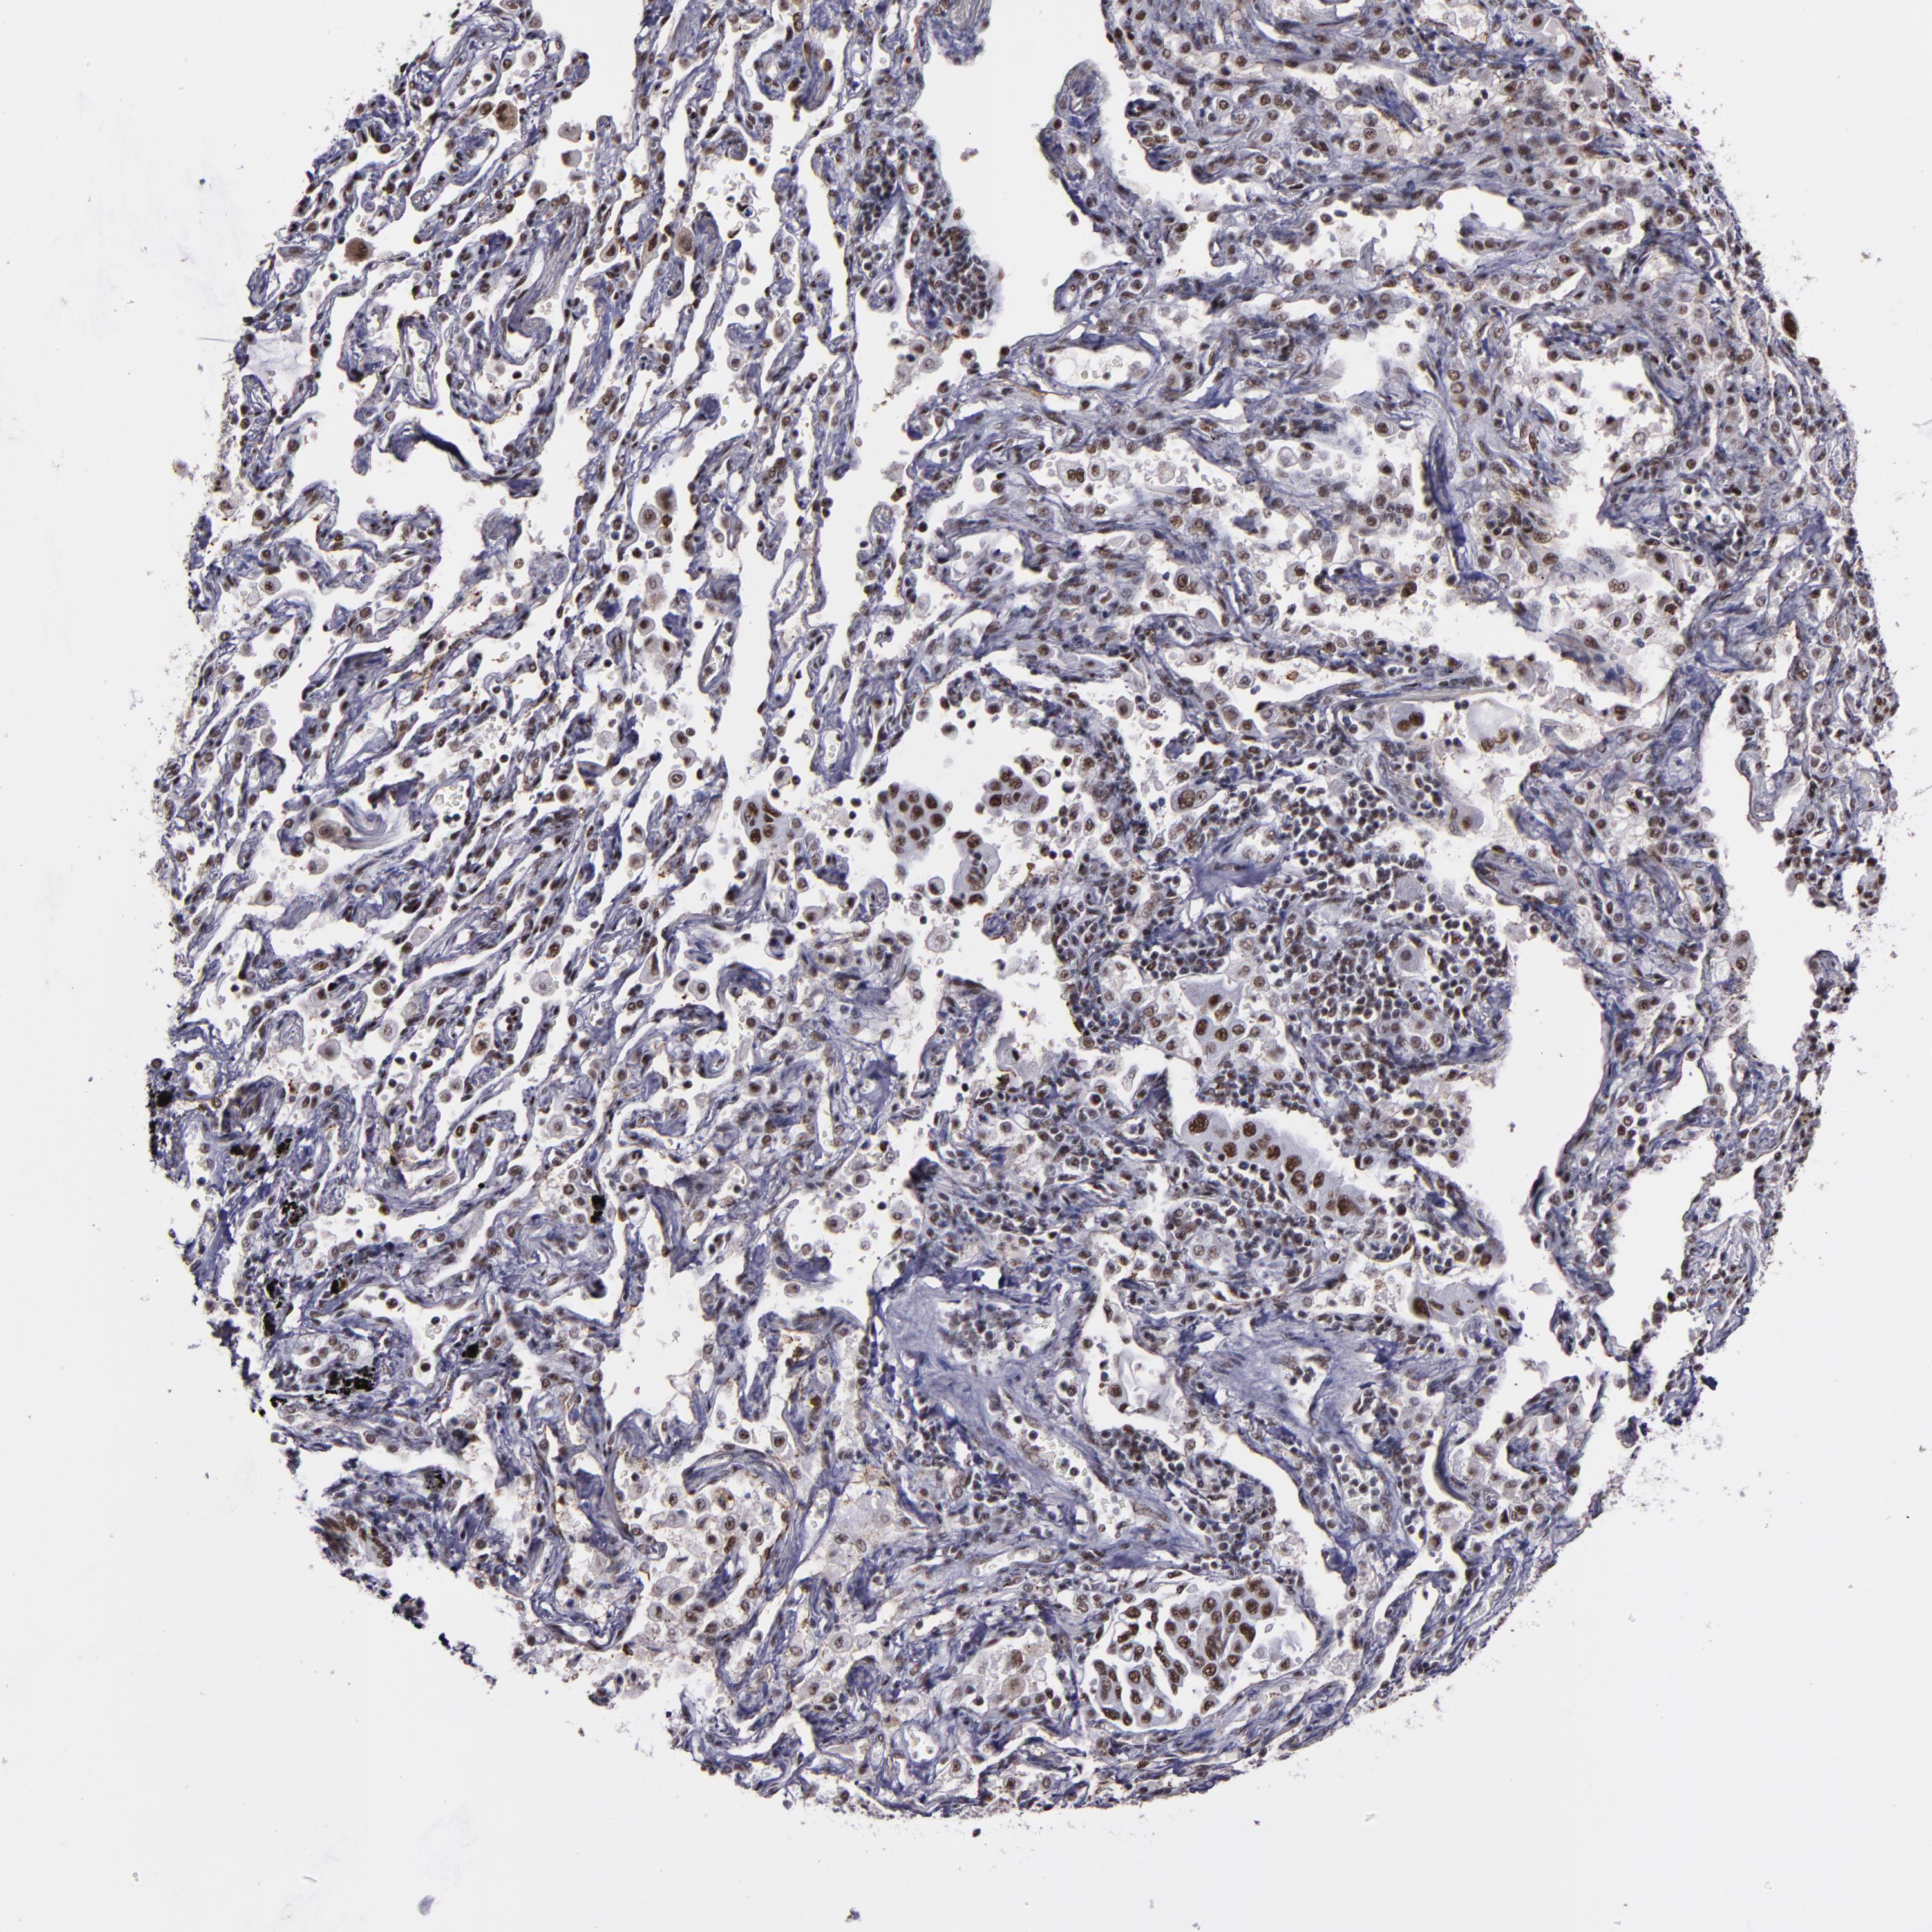

CANCER LUNG CANCER Show tissue menu

LUAD TCGA LUAD VALIDATION LUSC TCGA LUSC VALIDATION PROTEIN LUAD CPTAC PROTEIN LUSC CPTAC PROTEIN EXPRESSION

ANTIBODIES

AND

VALIDATION